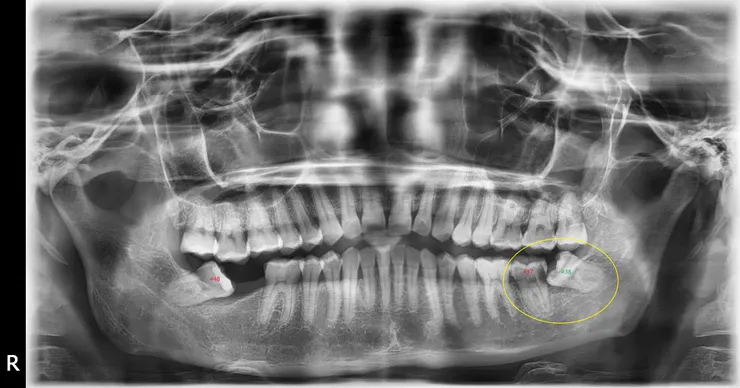

....一樣,拔智齒,對一般人是好的選擇,但在我跟您互動後,發覺這並不適合你(您會拖,拖到把根管治療的牙齒咬裂咬斷,您不會為了牙科治療而請假來看),所以後來我才跟你您說要拔蛀牙的那顆,而非智齒。

下面這篇文章裡,有平行時空裡的另一個下顎智齒造成蛀牙的臨床故事喔!證明我所慮有憑,臨床看太多了,謝謝每個來到我面前的病人,活生生演出錯誤的示範,病人真的是醫師的老師喔,請別太小看您自己。